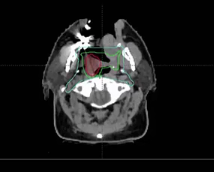

nasopharynx, MRI, PET, CT, NPX carcinoma, balloon procedure, right nasal pharyngeal carcinoma, 2A node, microscopic disease, T1, CLL, right parotid mass, squamous cell, right superficial parotidectomy, modified neck dissection, right temporal skin lesion excision, lymph node, ECE, bolus, dissecte...